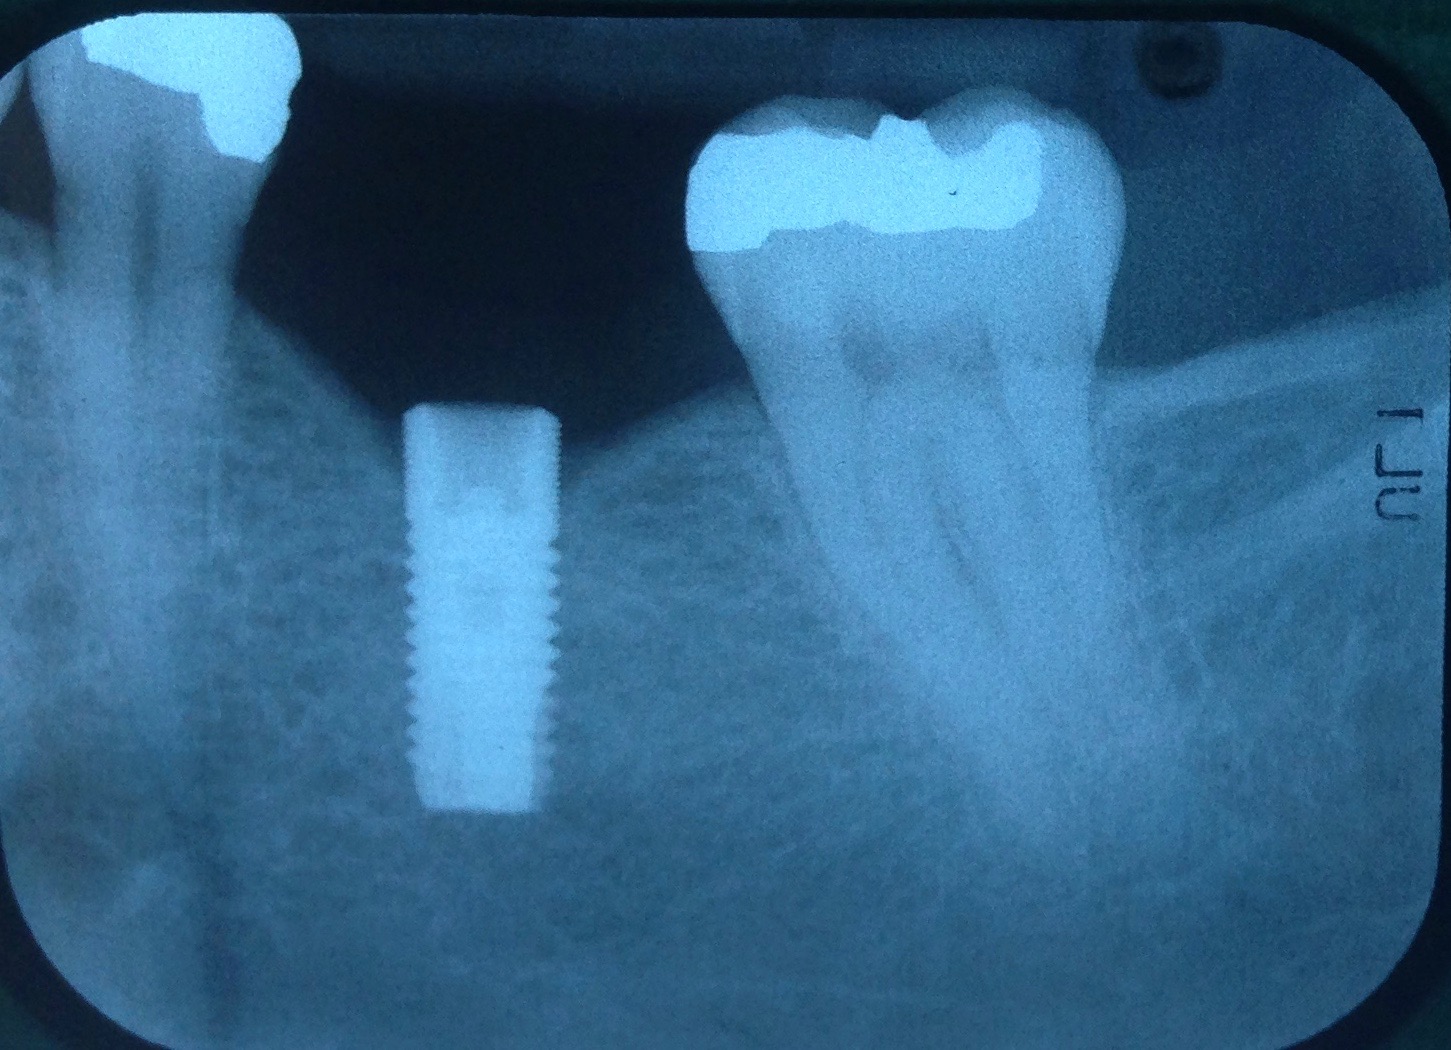

Fig 6. Radiograph following crown fracture.

Figure 6